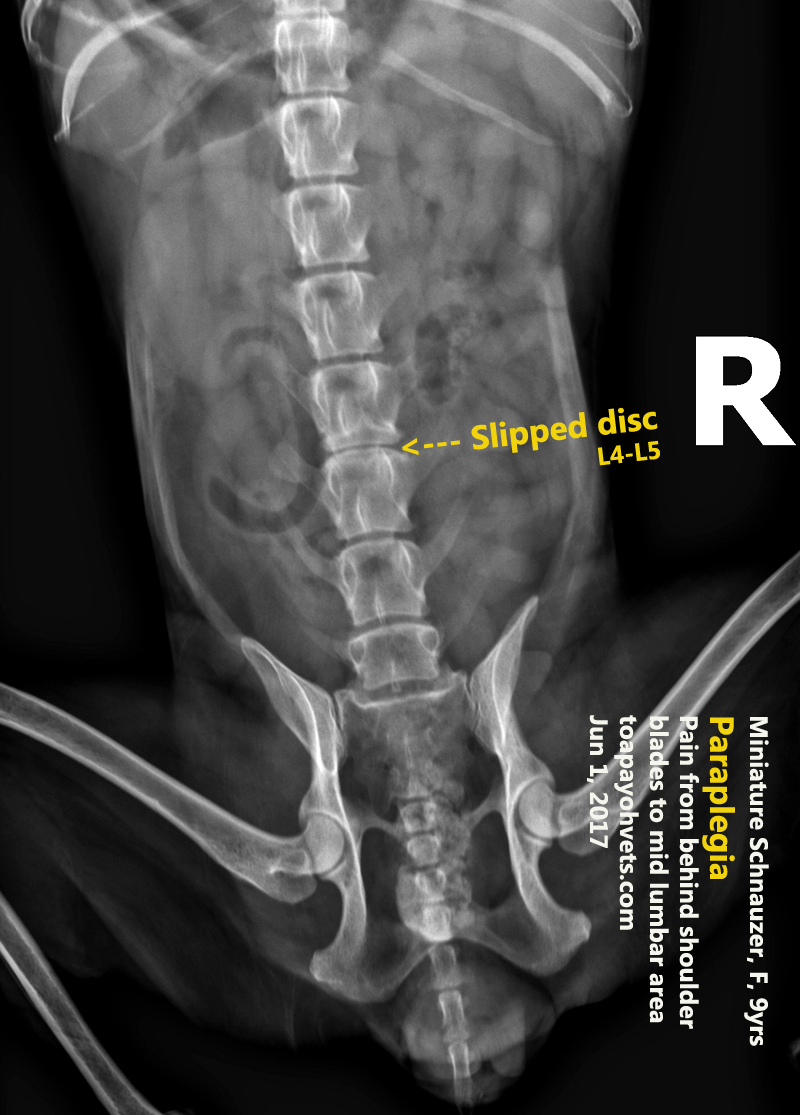

2010vets 3081. Slipped disc in a 9yearold, female intact Miniature Slipped Disc Dog X Ray Ivdd occurs when the intervertebral discs in the spine degenerate and put pressure on nearby nerves. If after examination, your dog is suspected to have a slipped disc, advanced imaging of the spine will be recommended for a definitive diagnosis. Chondrodystrophic breeds are most commonly affected, but ivdd can occur in any breed. Fortunately, early detection and proper treatment are. Slipped Disc Dog X Ray.

2010vets 3081. Slipped disc in a 9yearold, female intact Miniature Slipped Disc Dog X Ray Chondrodystrophic breeds are most commonly affected, but ivdd can occur in any breed. Intervertebral disc disease (ivdd) is a common spinal condition that affects many dogs. Ivdd is one of the most common causes of spinal cord injury in dogs. A veterinary neurology problem in dogs, better known as slipped discs, is usually caused by one of two reasons: Mri. Slipped Disc Dog X Ray.